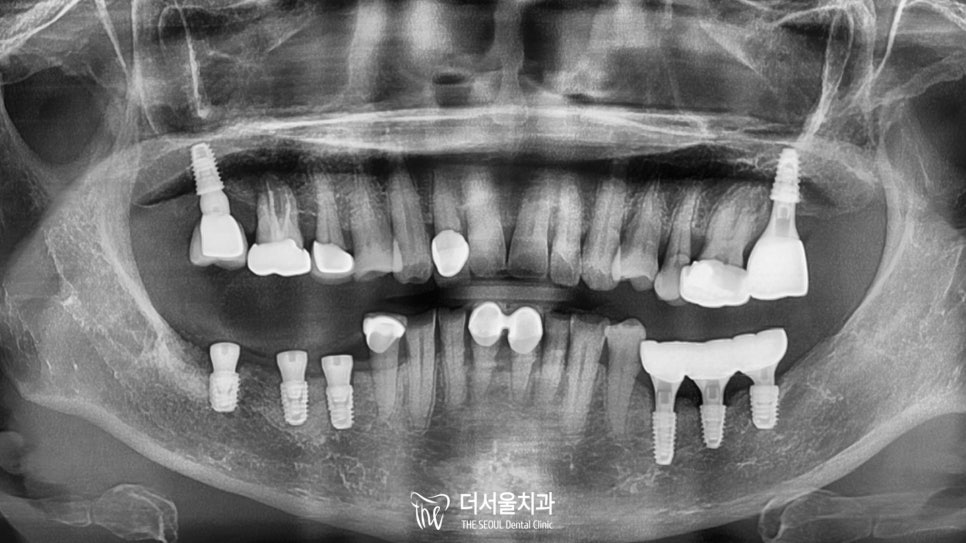

엑스레이 촬영을 통해 좀 더 자세히 살펴보니

빠져버린 치아 말고도 여러 문제들이 관찰되었습니다.

1) 곳곳에 심한 골소실

2) 대합치 정출

3) 심한 동요

전체적으로 구강 상태가 좋은 편은 아니었죠.